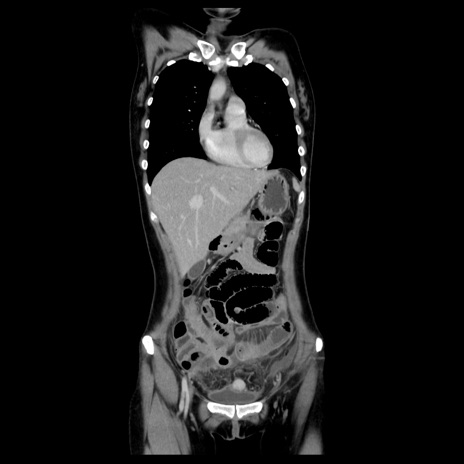

症例39(冠状断像)

【症例】40歳代女性

【主訴】上下腹部痛

【現病歴】2日目から下腹部痛あり。夜間は痛みで眠れなかった。昨日より上腹部痛と下痢が出現。臥位で痛みは軽快したため、休んでいた。本日になって臥位でも立位でも痛みが強くなってきたため救急要請。

【既往歴】子宮内膜症

【身体所見】部:平坦・軟、左上下腹部に圧痛あり、反跳痛あり。

【データ】WBC 21800、CRP 26.78

CT